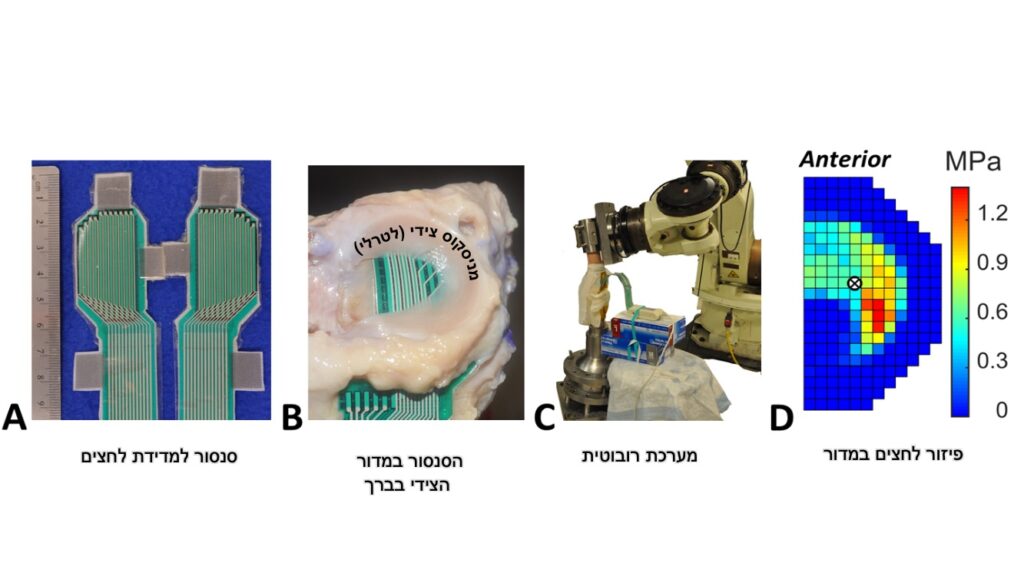

במסגרת המחקר בוצע הניתוח הסטנדרטי לשחזור רצועה צולבת קדמית עם שתל גיד פיקה על ברכיים מגופות שנתרמו למדע. לאחר מכן בוצעה בנוסף הפרוצדורה לחיזוק צידי (LET). בכל שלב בוצעו בדיקות על הברך באמצעות מערכת רובוטית ושימוש בציוד ומכשור מתקדם להערכת העומסים והכוחות שמתפתחים בברך בתגובה להפעלה של כוחות שונים בכיוונים שונים על הברך.